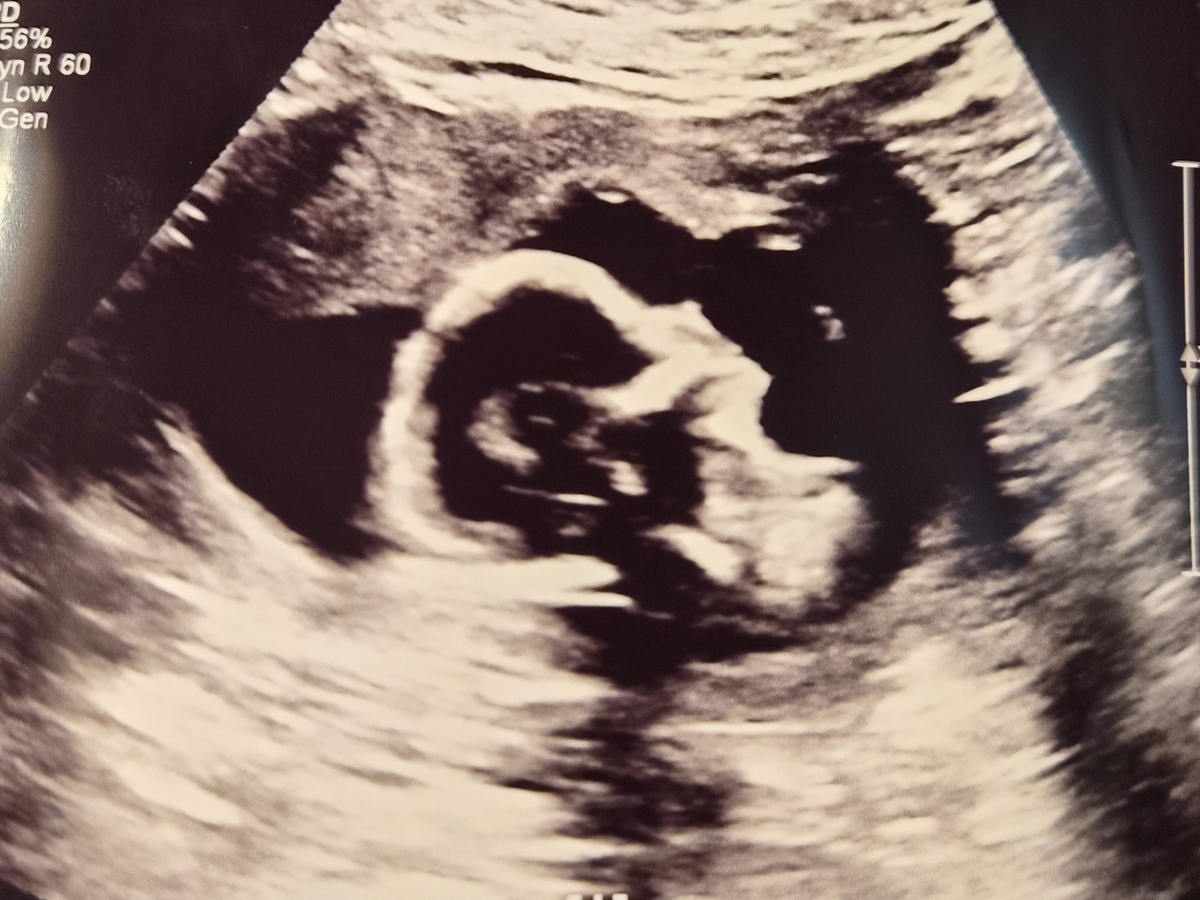

For those who may not know, Zach and I are expecting our third baby — our second little girl. During this pregnancy, we’ve faced several concerns that ultimately led to a diagnosis of placenta previa and placenta accreta. While previa is relatively common, accreta is rare and can be life-threatening for both mom and baby.

For the safety of both me and our baby, we have made the unexpected and very difficult decision to move back to California so I can be treated at UC Davis, where there are specialists experienced in managing placenta accreta. Baby girl will be delivered early, likely around 34–35 weeks. It is also very likely that I will undergo a hysterectomy at the time of delivery to prevent and control severe blood loss. We are preparing for a possible NICU stay for her, as well as ICU time and several days of hospitalization for me.